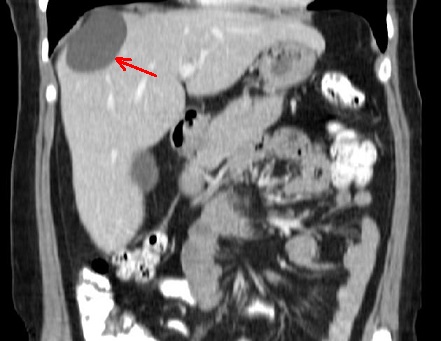

Image TDM de kyste du

foie : Image lesionaire arrondie , de taille variable souvent de

quelque centimetrique . Densite liquidienne de 0

a 15UH

Même cas en coupe coronal (

fleche rouge ) . La kyste est situe du foie droit

juste a inferieuse du coupole diapragmatique droit |